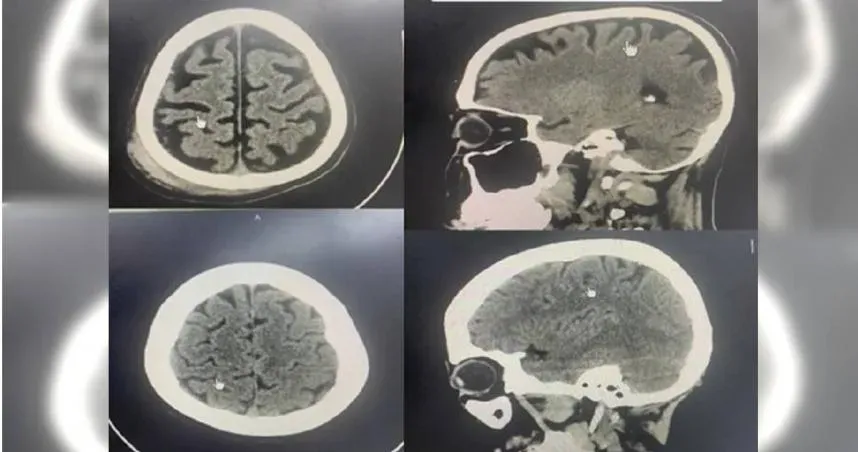

神經外科

大腦萎縮

腦部